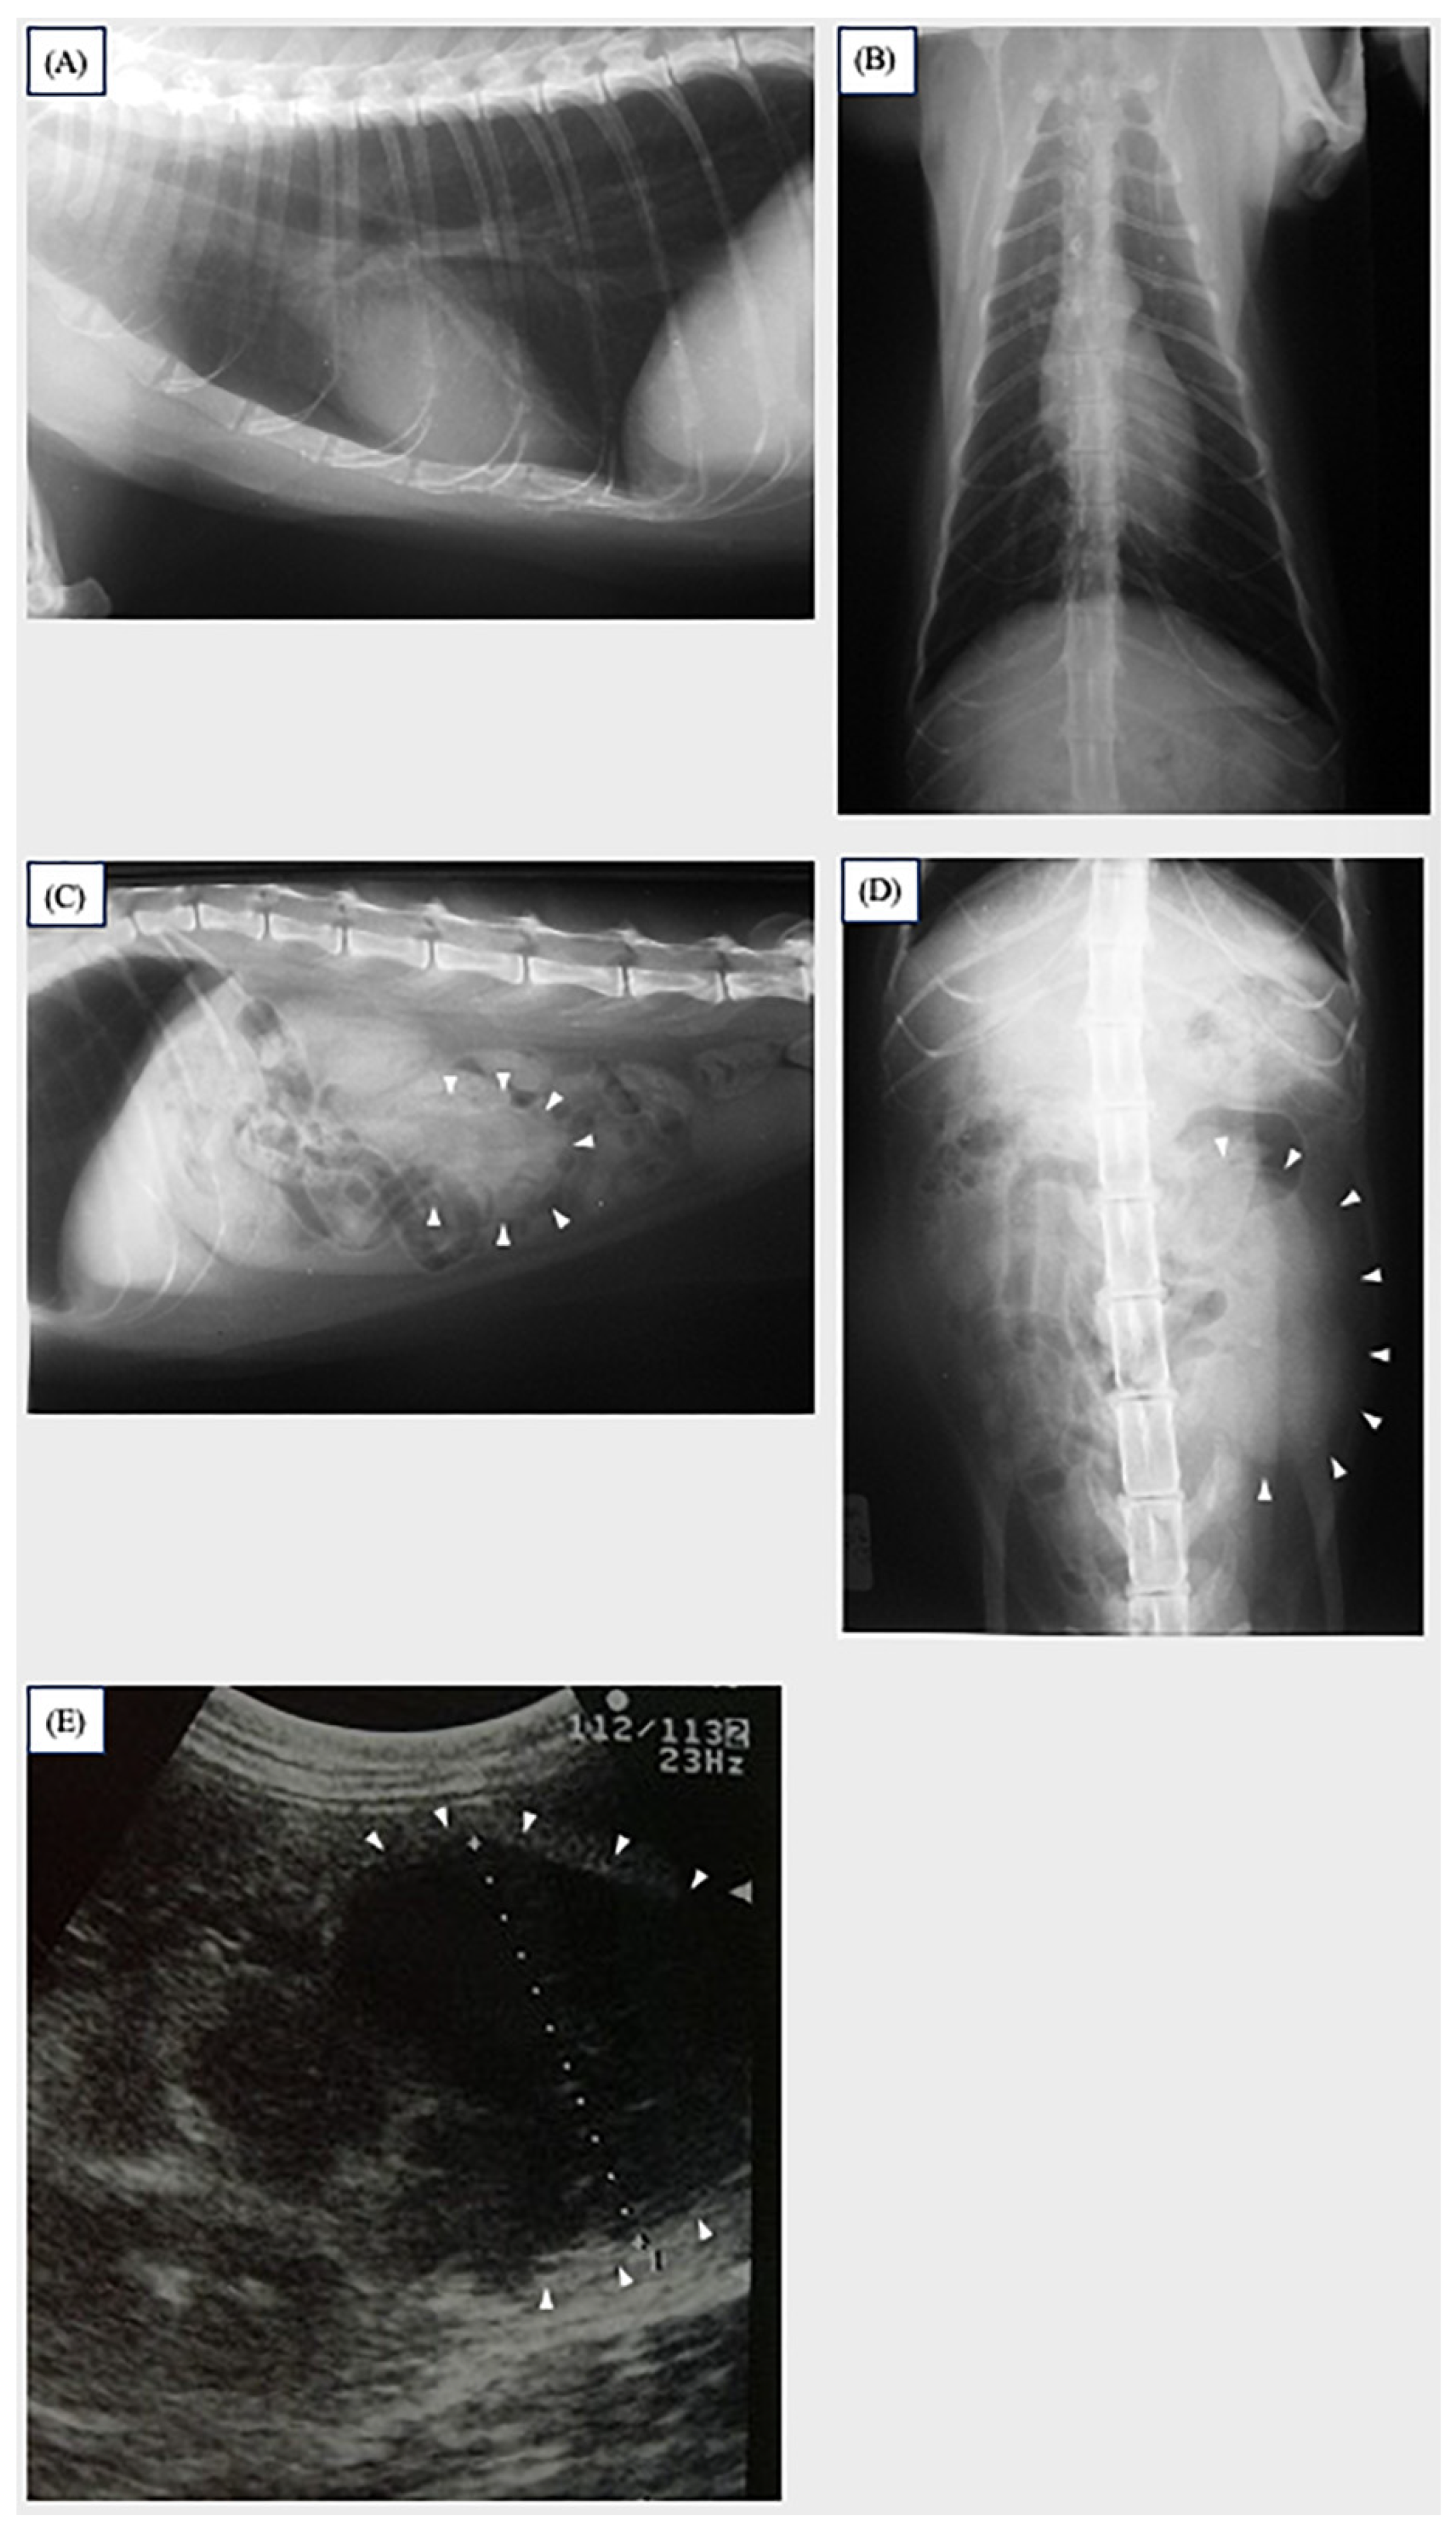

2. Case Description